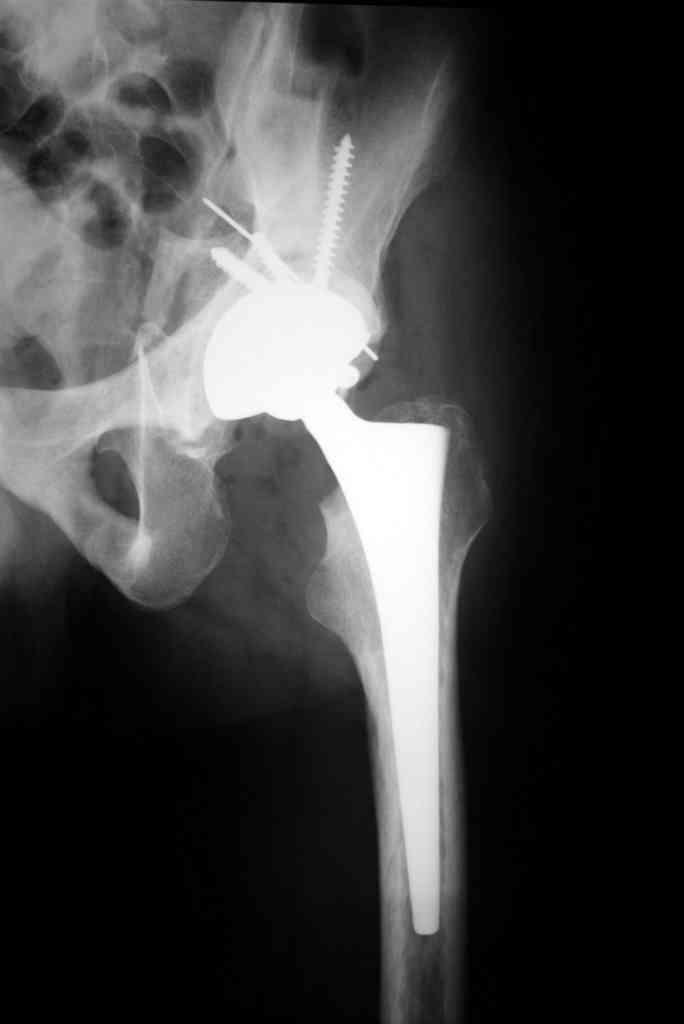

К сожалению, нередкая ситуация, мы предпочитаем выполнять операцию одномоментно - пластика задне-верхнего дефекта крыши ВВ собственной

головкой, установка вертлужного компонента бесцементной фиксации с обязательной дополнительной фиксацией винтами. Проблема будет в

восстановлении длины ноги, опыт показывает, что более 3-х см одномоментно восстановить очень сложно, и даже для этого потребуется широкая мобилизация бедра. В одном из номеров ж-ла Ортопедия травматология России мы опубликовали наш подход и р-ты лечения у больных с последствиями перелома ВВ.

Прилагаю в качестве иллюстрации одну из последних операций.

С уважением, Р.Тихилов

Уважаемый д-р Рунков А.В.(извиняюсь что не по имени-отчеству), Я всегда пользуюсь передним доступом на боку, но при этом обязательно

выполняю задний релиз - либо из этого же доступа после резекции головки, либо путем мобилизации сзади при внутренней ротации бедра. Критерием

достаточности является возможность свободно "оторвать" бедро в среднем ротационном положении. После такой мобилизации при сгибании бедра и

наружной ротации достаточно легко выполнить фиксацию головки в зону дефекта ВВ. Если это не удается - то это можно сделать сзади через

небольшие проколы м.тканей. Есть один нюанс - при застарелых переломо-вывихаха достаточно сложно найти ВВ, так отшлифовывается новая

ВВ, что создается полное впечатление об ее истинности, будьте предельно внимательны. Как только Вы нашли истинную ВВ, Вы ее начинаете

обрабатывать фрезами, слегка "подрываясь" вверх, таким образом, уменьшается размер дефекта, подлежащий пластике. Поэтому головки всегда

хватает. Плюс к этому то, что Вы "наскоблили". Ни разу не пользовались аллографтами, но нам проще - у нас свой банк. П/о ведение зависит от

степени покрытия чашки и прочности ее фиксации. Как правило, касание пола с первых дней, частичную нагрузку разрешаем через 6 недель, полную

- через 12 недель. Если есть сомнения, то полная нагрузка через 4 м-ца.